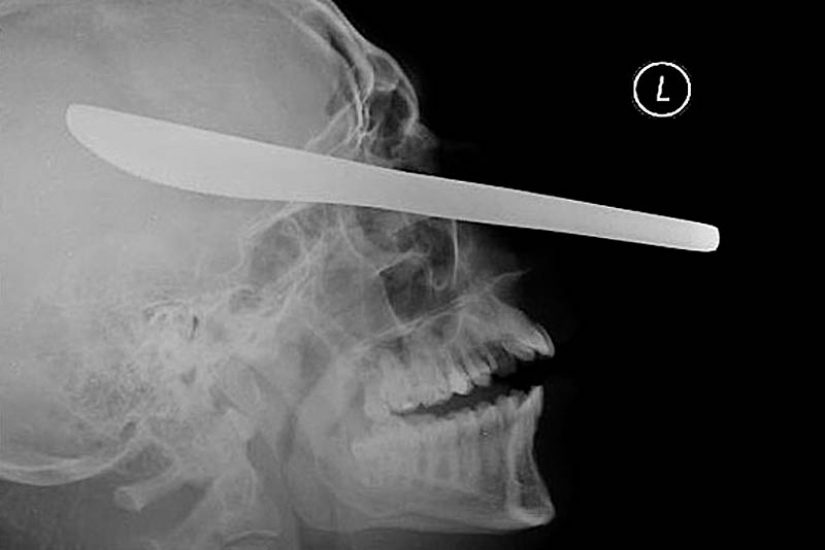

11. The spear from the harpoon, caught in the head of a 16-year-old boy fishing.

15. Knife in the head 10 year old boy. The boy survived.

18. 12-centimeter knife in the skull of a teenager.